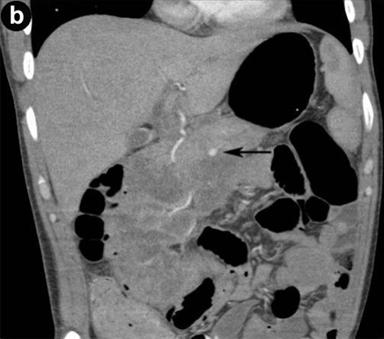

Duplex US and PVPCT are the most common first-line investigations in assessing acute pancreatitis. To enable detection of pseudoaneurysms, US examination must include pulsed or colour Doppler (duplex US) of all cystic masses to distinguish a pseudocyst from a pseudoaneurysm [20]. The sonographic appearance of a pseudoaneurysm changes when clot develops within its lumen rendering the diagnosis very difficult even with colour Doppler [21]. In the present series, US with colour Doppler failed to detect the presence of a pseudoaneurysm in two patients which were later diagnosed on PVPCT and arterial phase CT. Similar results have been observed in other studies, and most clinicians would conclude that the diagnostic value of Doppler US in the detection of pseudoaneurysms complicating pancreatitis is limited [22, 23]. Although PVPCT is a suitable non-invasive method for detecting pseudoaneurysms [22, 24, 25, 26], its role in the diagnosis of pseudoaneurysms is limited by its failure to identify smaller pseudoaneurysms [23, 27, 28]. In the present series, PVPCT failed to detect small pseudoaneurysms in five patients which were later diagnosed on arterial phase CT (Figure 3).

|

Figure 3. a. Portal venous phase contrast enhanced computed tomography (PVPCT) in a patient with a small pseudoaneurysm which is not demonstrated. b. Arterial phase computed tomography in the same patient demonstrates a small pseudoaneurysm (arrow). |

Arterial phase CT is a suitable first-line investigation for diagnosing pseudoaneurysms associated with pancreatitis with a similar sensitivity rate that of angiography [28, 29, 30]. In the present series, arterial phase CT detected all pseudoaneurysms when used as a first-line (n=2), second-line (n=4) and third-line investigation (n=1). Arterial phase CT has the additional benefit of planning further management by clearly demonstrating the arterial anatomy, providing a roadmap for further intervention. This allows for targeted visceral angiography as well as the identification of difficult cases prior to intervention. In this study, not all patients (n=3) underwent an arterial phase CT to confirm resolution of the pseudoaneurysm. One reason for this non-uniformity follow-up was due to the fact that two patients were embolised prior to 2007 when follow-up with arterial phase CT was not practiced routinely and one patient underwent a PVPCT to exclude an intra-abdominal collection where the pseudoaneurysm was shown to have resolved.